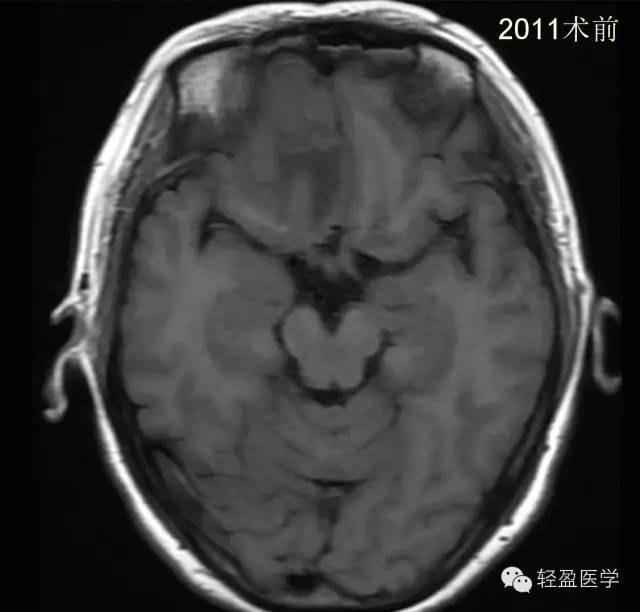

【病例】颅内肿瘤,脑内?脑外?

病理为:小细胞恶性肿瘤,考虑为(外周)原始神经外胚层肿瘤,(复发)。以下是病例结果及分析。